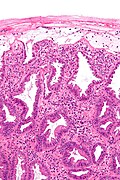

Microscopic

Features:[13]

- Heaped necrotic surface epithelium.

- Described as "volanco lesions" - this is what is seen endoscopically.

- PMNs in lamina propria.

- +/-Capillary fibrin thrombi.

Notes:

- Pseudomembranes arise from the crypts.

- Rarely have (benign) signet ring cell-like cells.[18]